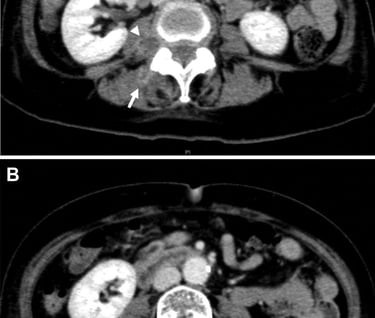

However, like all medical procedures, CAC is not without its challenges. The article provides a detailed account of a rare case where a patient developed symptomatic septicemia following the CAC procedure. This occurrence, while uncommon, underscores the importance of meticulous post-operative care and monitoring.

In the highlighted case, the patient presented with high fever and chills the day after the procedure. Further investigations revealed inflammation and infection of the treated great saphenous vein. The medical team opted for surgical excision of the treated vein to address the issue.